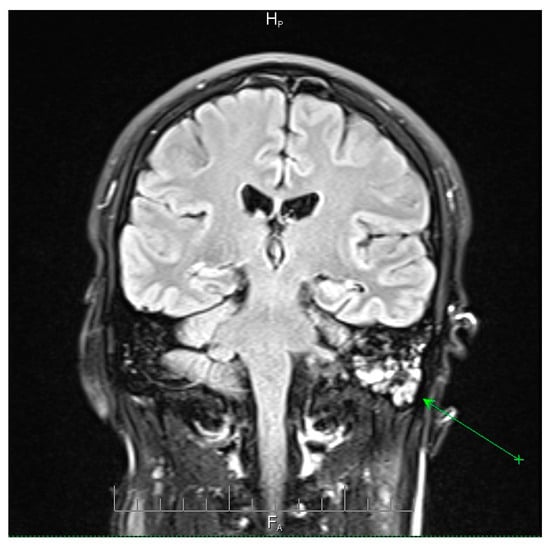

Fulminant Multidrug-Resistant Streptococcus pneumoniae Meningoencephalitis After Elective ENT Surgery: A Case Report

by Corina-Ioana Anton, Madalina Maria Zamfir, Alexandru Ghiță and Mihaela Raluca Mititelu

Pneumococcal meningoencephalitis is a severe infection associated with high morbidity and mortality. Although typically community-acquired, postoperative cases following elective ENT surgery are exceedingly rare. Antimicrobial resistance (AMR) among Streptococcus pneumoniae further complicates management, and missed opportunities for vaccination represent preventable risks. We report a case of a 41-year-old man with multiple comorbidities who developed fulminant S. pneumoniae meningitis 48 h after septoturbinoplasty. The clinical course was atypical, with altered consciousness but no classical meningeal signs, necessitating urgent intubation and intensive care admission. Cerebrospinal fluid cultures identified an MDR pneumococcal strain resistant to penicillin and macrolides but susceptible to vancomycin and meropenem. Empirical therapy with vancomycin and meropenem, combined with adjunctive corticosteroids and multidisciplinary ICU care, led to complete neurological recovery. This case highlights a rare but life-threatening postoperative complication and underscores two critical lessons. First, the growing challenge of multidrug-resistant pneumococcus requires timely recognition, aggressive empiric therapy, and access to effective agents. Second, the absence of pneumococcal vaccination in this high-risk surgical patient illustrates a preventable gap in care. Integrating vaccination screening into preoperative evaluations may reduce the risk of catastrophic postoperative CNS infections. Full article

Show Figures

Figure 1